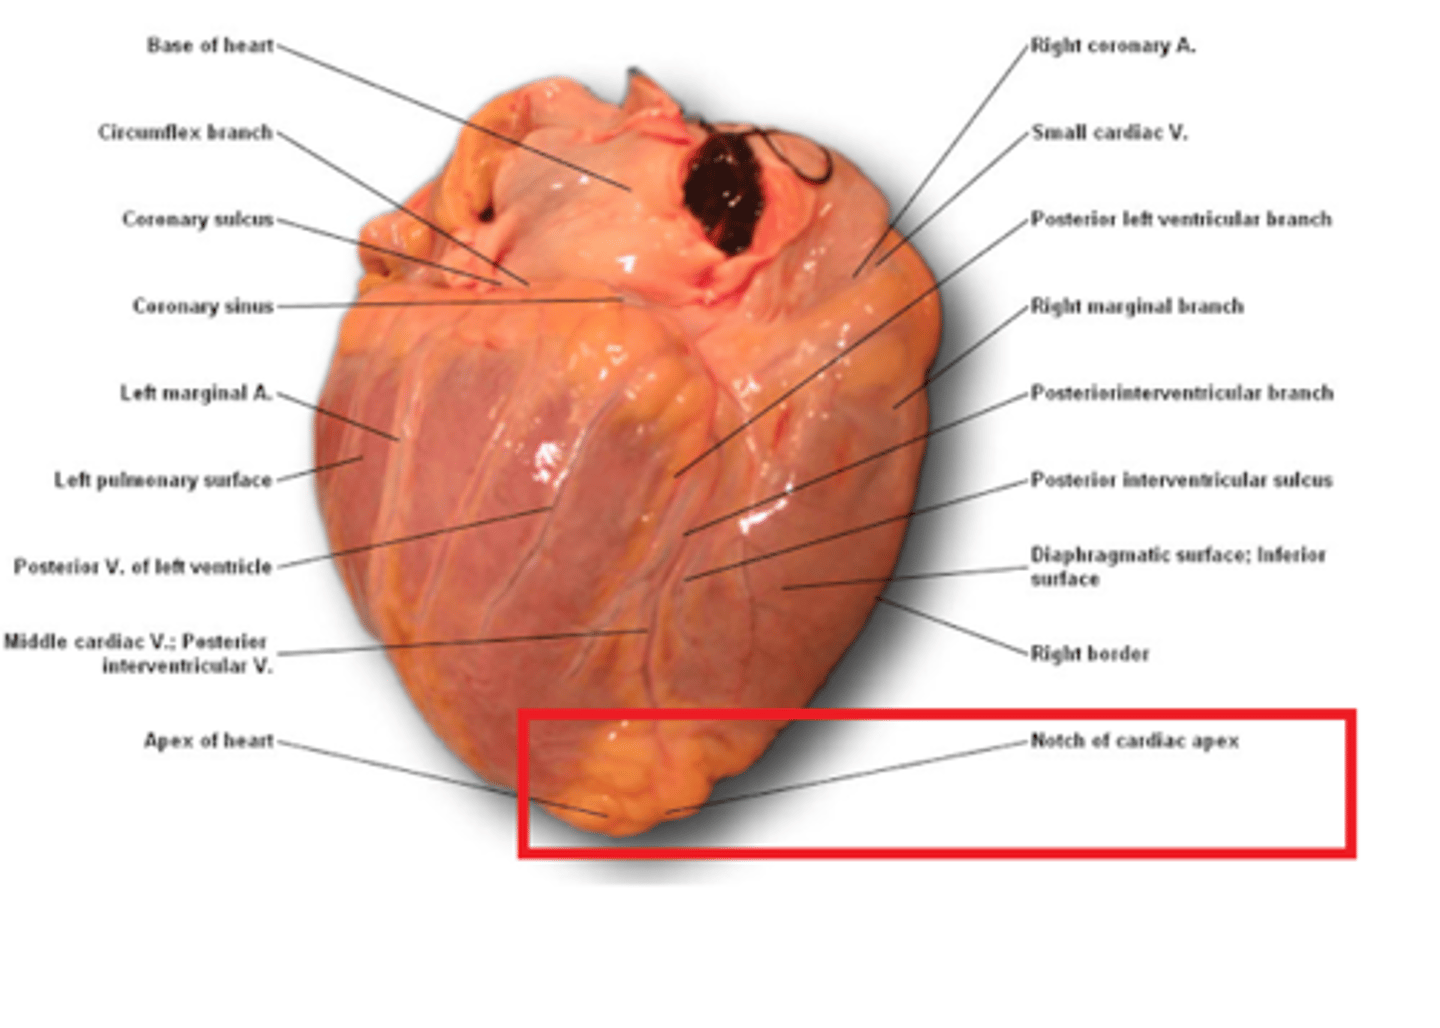

bruzda międzykomorowa tylna

posterior interventricular sulcus

Jak biegną bruzdy międzykomorowe?

od bruzdy wieńcowej w kierunku koniuszka serca

Co tworzą bruzdy międzykomorowe w okolicy koniuszka serca?

wcięcie koniuszka serca

wcięcie koniuszka serca

notch of cardiac apex

bruzda wieńcowa

coronary sulcus

Jak biegnie bruzda wieńcowa?

w płaszczyźnie prostopadłej do osi serca